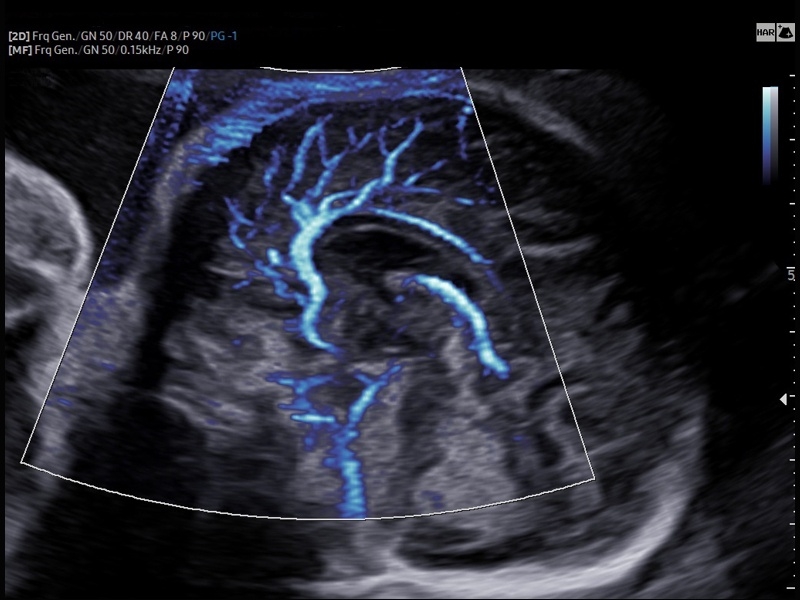

Ультразвуковой сканер V8-RUS является экспертным классом (премиальный уровень) и производится компанией Samsung Medison. Сканер V8 обеспечивает превосходное качество изображения благодаря использованию технологии Crystal Architecture™, которая включает в себя передовое аппаратное обеспечение, монокристальную технологию изготовления датчиков и сложную программную обработку ультразвуковых лучей.

• Технологии визуализации: MV Flow, LumiFlow, SEE Stream, Panoramic

• Модуль MV-Flow – программа (режим), позволяющая визуализировать кровоток в микроциркуляторном русле с высоким разрешением без использования контраста.

• Модуль LumiFlow – программа отображения кровотока с объемной графикой для лучшего понимания архитектоники сосудистого русла.

• Модуль Crystal Vue Flow- программа реконструкции прозрачного 3D УЗИ, которое получается при одновременном усилении внутренних и наружных структур. Применяется для визуальной оценки состояния плода и матки, помогает лучше идентифицировать мягкие ткани и кости. Так же визуализирует объемный кровоток.